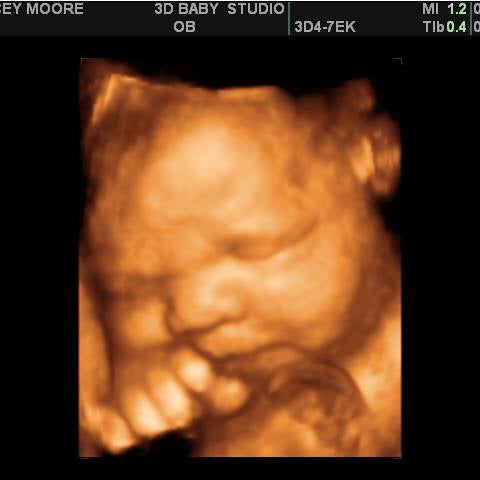

My Sunshine Baby is dedicated to providing the very best expereince to pregnant mothers in the Charlotte NC area. Please note that our 3D ultrasounds and 4D ultrasounds can only be performed on pregnant women who are under the care of a physician. No need to argue endlessly about who your baby looks like even before birth the 3D and 4D ultrasound images will allow you to view vivid images of your baby.

Sweet Pea 3D of Concord Charlotte area North Carolina offers the finest 3D4D prenatal ultrasound. With the 3D and. Welcome To 3D Baby Ultrasound Studio We Offer 2D 3D 4D High Definition Sessions For Expectant Families To Visit With Their Newest Family Member In A Relaxed Family Friendly Setting.

Overall a great and fun experience. There is no time more precious and cherished during the pregnancy than the time that the mother-to-be gets to spend looking at her child through the miracle. Laura was very gentle attentive and made sure we had amazing pictures even with baby sleeping.